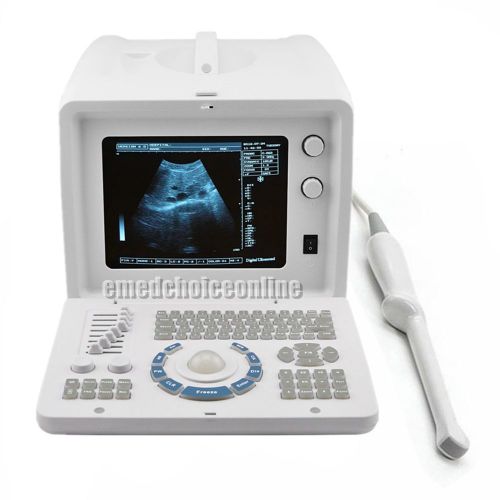

3D PC Plateform Based Full Digital Portable Ultrasound Scanner+3.5mhz convex pro

3D PC FULL digital Portable ultrasound scanner machine 3.5mhz Convex 3Y WARRANTY

Internal 3D 3.5mhz convex+6.5mh Transvaginal Portable Ultrasound Scanner machine

Internal 3D 3.5mhz convex probe Portable Ultrasound Scanner machine warranty

FDA Portable Digital Ultrasound Scanner CONVEX PROBE 3D software optional linear

CE FDA Full Digital Portable Ultrasound Scanner+Transvaginal Probe +3D Software

Portable Ultrasound Scanner Sysytem Machine +7.5MHZ Linear probe+WARRANTY

CE FDA Ultrasound Scanner Machine +Convex Probe +Free 3D Software + 2ys warranty